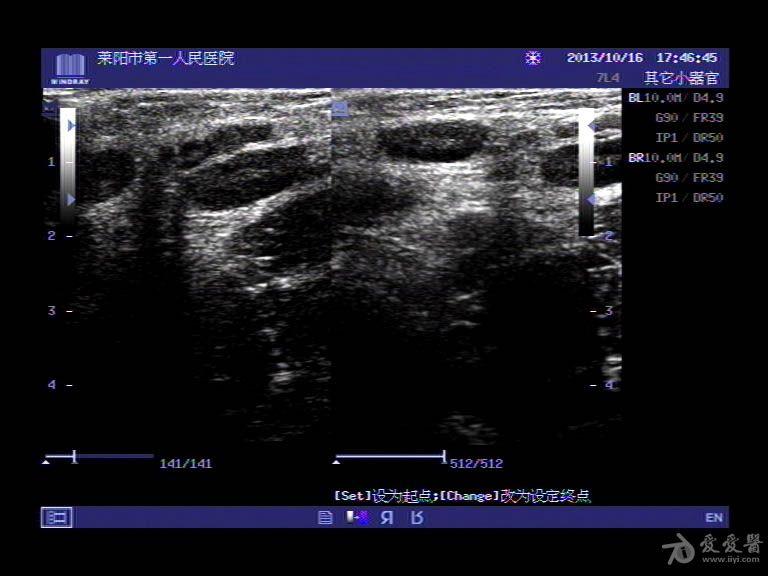

超声入门贴179-----腹股沟淋巴结肿大